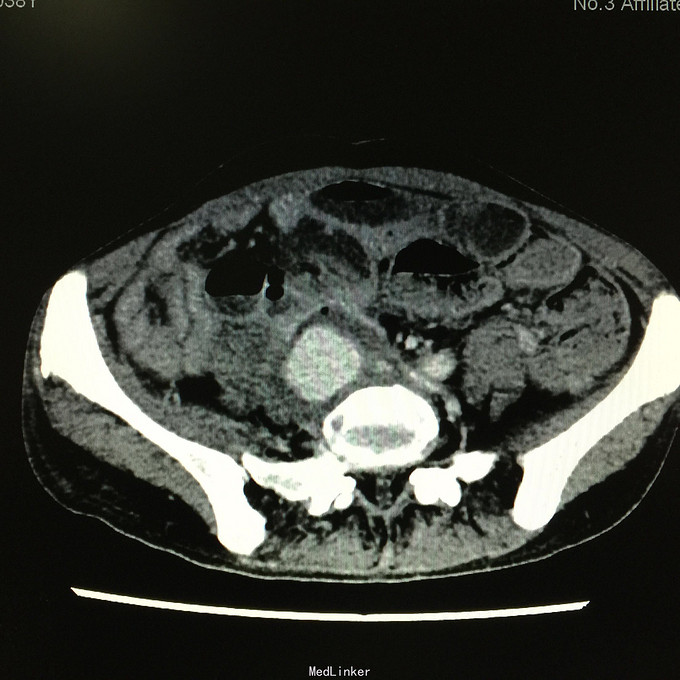

查体无特殊。 辅助检查:中下腹CT平扫+增强+CTU+CTA示:1.右输尿管中上段病变,考虑恶性病变,周围多发淋巴结转移,髂总动脉及髂外动脉起始部、髂内动脉中上段受侵闭塞,右侧腰大肌可疑受侵;建议输尿管镜检查;右肾重度积水,右肾功能明显受损。2.CTA示:右肾动脉纤细,肝右动脉起源于肠系膜上动脉。3.子宫体密度不均匀,建议MRI检查。中下腹MRI平扫+增强+MRU检查结果类似。

患者术后2月出现反复臀部疼痛,左侧为主,疼痛跑迷宫为隐痛,于翻身及活动时加重,卧床休息可稍缓解,多于下午出现,伴有发热,最高达39℃,在当地医院予“氟康唑”及止痛治疗后稍有缓解,但仍反复发热。后疼痛加剧,并出现双下肢疼痛,以大腿外侧为主,无间歇性跛行,无小腿及双足麻木疼痛不适,行对症治疗后效果不佳,于2015-10-9再次返院,予消炎止痛、营养支持及营养神经等治疗。查CT及MRI均提示骶髂关节炎症及腹膜后巨大病变,右侧髂总动脉及髂内、外动脉上段、右侧腰大肌受累。2015-10-15 14:00患者出现右下肢剧烈疼痛、右下肢乏力和麻木,随后出现2次血便,每次量约100ml,暗红色,无腹胀、腹痛等不适,查血提示白细胞 28.17*10E9/L,中性粒绝对值 25.33*10E9/L,血红蛋白56g/L,予止血、输血、抗真菌、止痛等治疗。19:00再次出现右下肢剧烈疼痛伴右下腹痛,查体:BP 80-90/50-60mmHg,P 100-106次/分,R 23次/分,SpO2 100%。右下腹轻压痛,反跳痛阴性,右下肢蹲背伸及踝背伸肌力II-III级,立即行全腹CT检查,示右髂总动脉假性动脉瘤破裂,予加强输注浓缩红细胞及补液支持治疗。清介入科会诊,考虑脓肿和感染为介入血管腔内支架置入治疗的禁忌症,建议予血管外科行开放手术,予患者及家属沟通,并转外院血管外科进一步治疗。